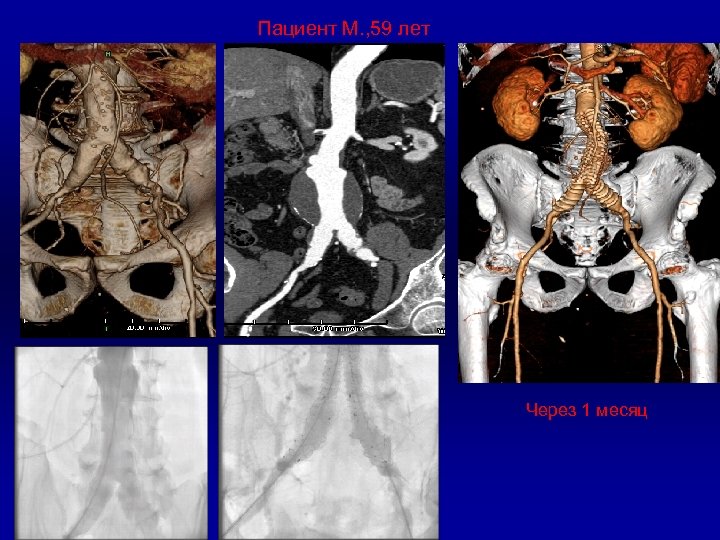

Пациент М. , 59 лет Vascutek Anaconda Через 1 месяц